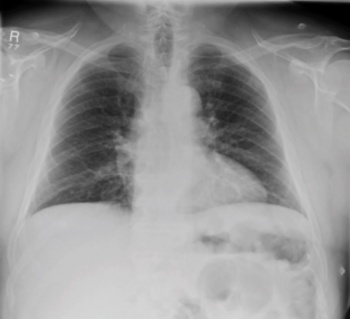

ABG showed type 1 respiratory failure picture with PO2 of 9.40, PCO2 was 4.68 and saturation of 92%, lactate was 2.2. Septic work up including full blood count, liver functions and electrolytes were normal. A postero-anterior chest x-ray (see Figure 1) was performed, reported normal with no rib fracture or pneumothorax. Urine dip analysis showed one plus blood. ECG performed showed sinus tachycardia.

Figure 1. X-ray chest – no evident rib fracture

Figure 1. X-ray chest – no evident rib fracture(click to enlarge)